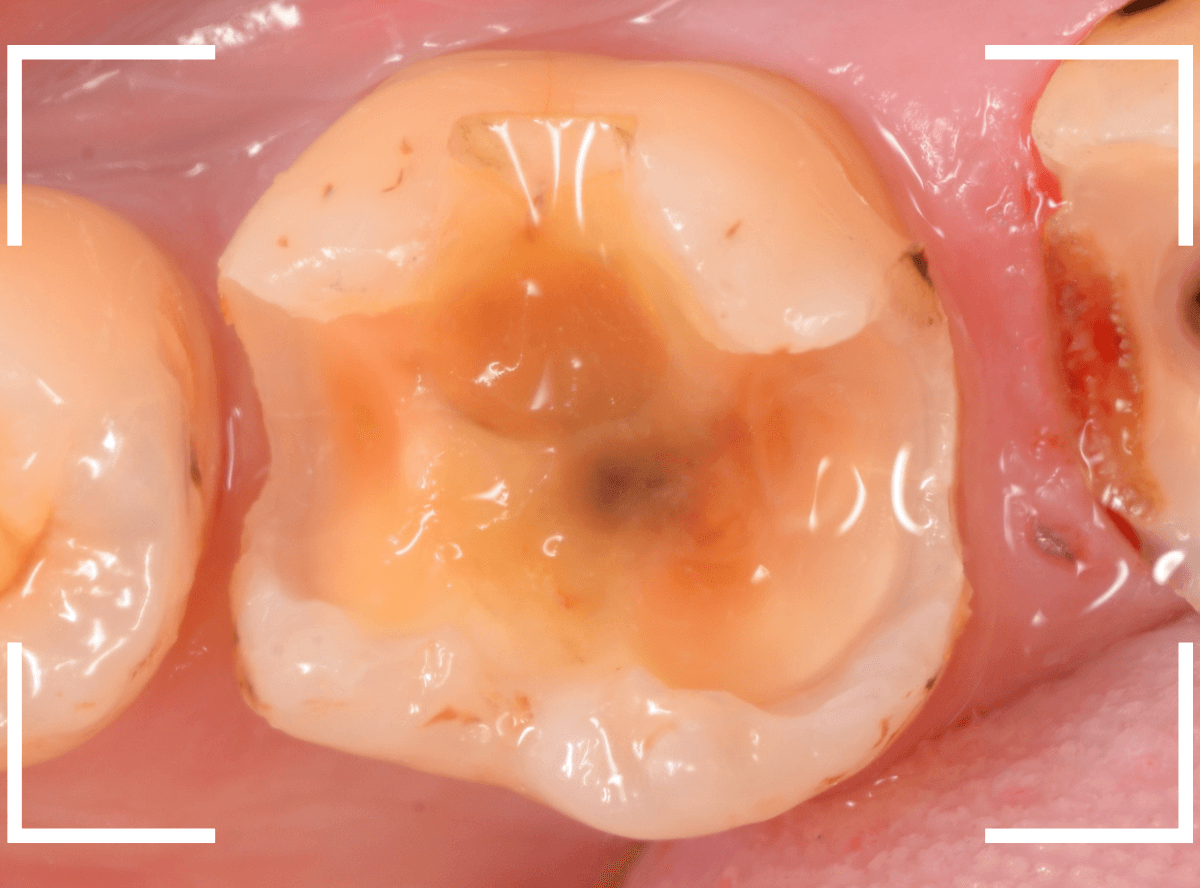

手前の歯のつめ物も外します。

こちらもお薬が入っていますが、外して中を調べます。

こちらは中も問題なかったです。